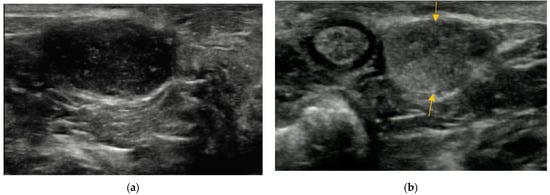

3.2. Content of Anal Sacs

3.3. Size and Shape of Anal Sacs

3.4. Wall of Anal Sacs

3.5. Adverse Findings

4. Discussion